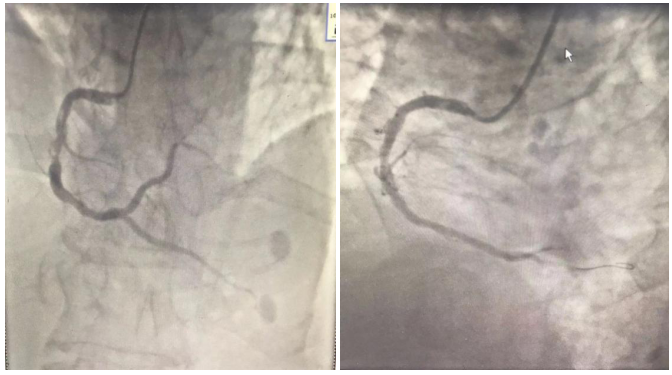

患者入院后指脉氧低 , 心率快 , 复查血气分析 , 氧分压 57.0 mmHg , 二氧化碳分压50 mmHg , 患者多次复查血气分析提示低氧血症 , 患者入院前行胸片检查提示两肺间质性改变 , 右侧膈肌升高 , D-二聚体:600 ug/L , 高度怀疑患者合并肺栓塞 , 急查肺动脉CTA显示右肺上叶尖段肺动脉栓塞;

胸部CT:1.两肺多发结节 , 建议随诊、复查 。 2.右肺下叶后基底段钙化小结节 。 3.两侧局部胸膜肥厚 。 4.符合动脉硬化表现 。 5.肝内低密度影 , 考虑囊肿 。

补充诊断:1.右肺上叶尖段肺动脉栓塞;2.肝囊肿;3.脂肪肝 。

图1 , 右肺上叶尖段肺动脉栓塞

患者CT提示肺栓塞 , 目前不明确发生栓塞的时间 , 且患者高龄 , 生命征相对平稳 , 心肌三项、NT-proBNP升高 , 危险分层属于中高危 , 无溶栓指征 , 给予抗凝治疗 。